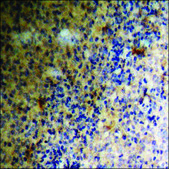

Anti-phospho-PDGFR β (pTyr740) antibody produced in rabbit

ELISA, IHC, WB

ELISA: 1:5000, immunohistochemistry: 1:50-1:100, western blot: 1:500-1:1000

The antiserum was produced against synthesized peptide derived from human PDGFR beta around the phosphorylation site of Tyr740.

Immunogen Range: 711-760